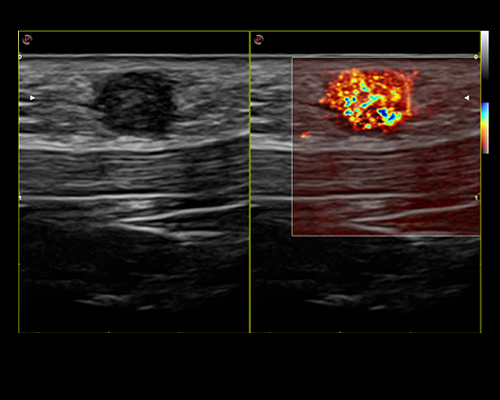

Research and successfully implement the limitless ultrasound technologies such as MicroE – Detect microcalcification; Xstrain4D – Cardiac strain 4D; XSTIC – Spatial-Temporal Image Correlation

MyLab X8 eXP integrates latest technologies, delivering high level of image quality with optimal workflow, efficiency